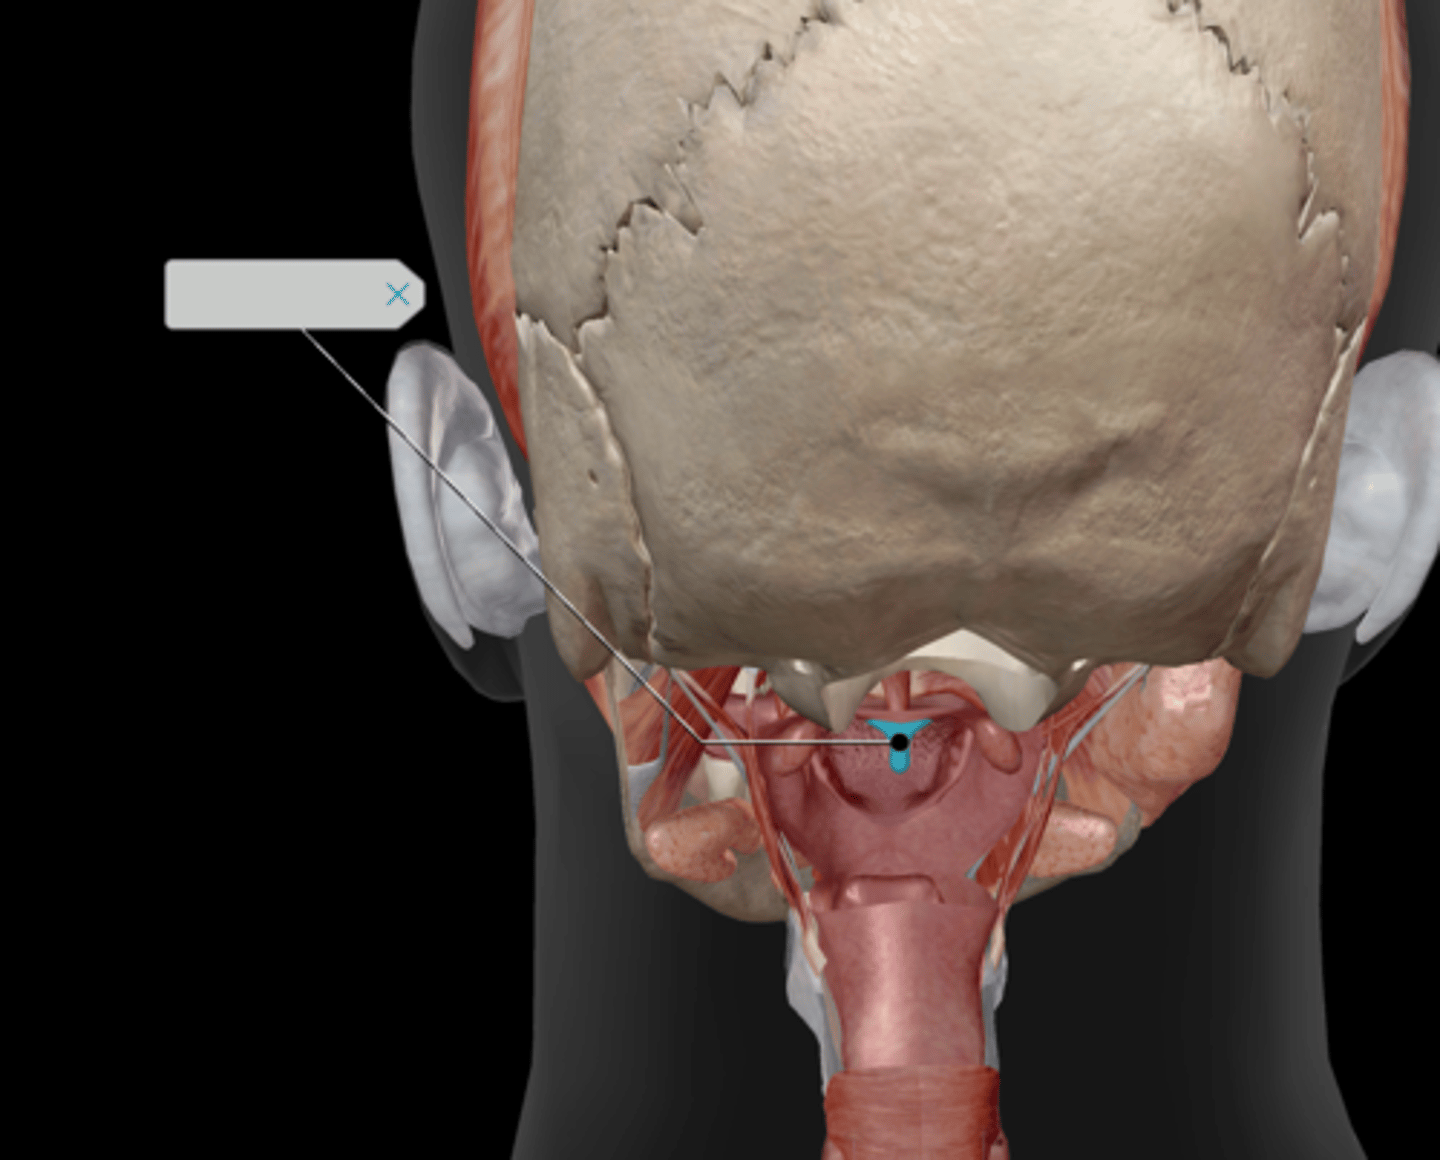

Epiglottis

Uvula